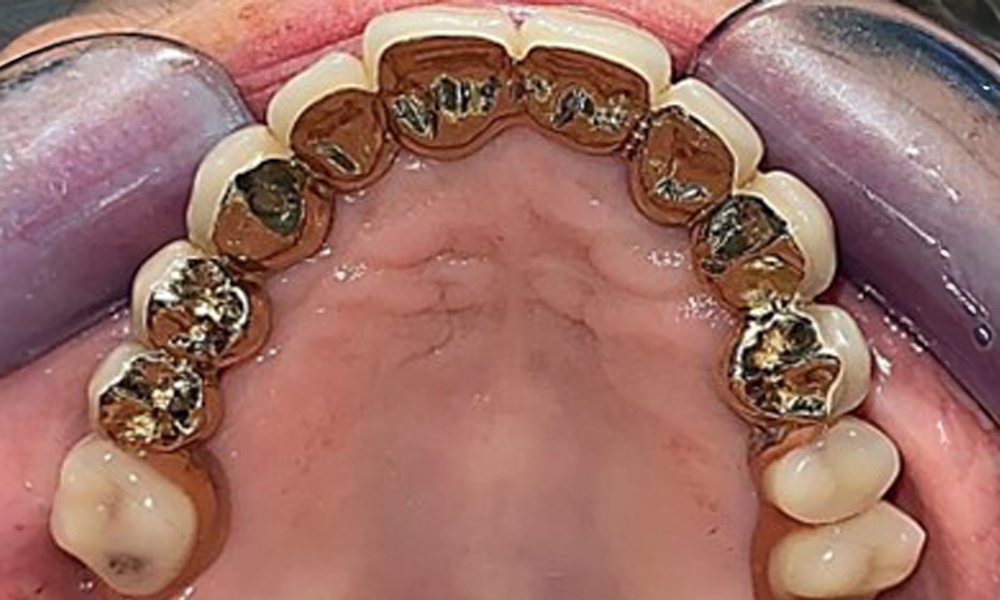

Occlusal view: Maxilla with removable, palateless denture.

Fig. 3: Occlusal view: Maxilla with removable, palateless denture.

The patient was fitted with a combined removable maxillary telescopic prosthesis more than 25 years ago (Fig. 1, Fig. 2, Fig. 3) and is very happy with her dentures. The patient has an adequate fixed denture for the mandible (Fig. 4).

The dental findings are as follows: Combined removable implant and tooth-supported telescopic prostheses on implants 15, 13, 21, 23, 24, 25 and tooth 11 (Fig. 1, Fig. 2, Fig. 3). The patient was fitted with a fixed mandibular denture. Adequate bridges were present over 37 to 34 and 45 to 47 (Fig. 4), the crown margins were intact and there were no active caries. A composite filling with a marginal gap was present on tooth 43. There was mandibular gingival recession, exposing 1 to 3 mm of root surface. This also applies to 11.